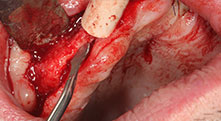

Could you give us a few surgical tips and tricks from your hospital?

Bratu: We like to use the sandwich technique for augmentation in the lateral mandible. A bone cover is prepared with the piezo saw and the crestal fragment is fixed with microscrews. We place a mixture of autologous bone and xenogenic bone replacement material in between. This works very reliably. You should always ensure sufficiently dimensioned vertical cuts when splitting the alveolar ridge in the mandible. Otherwise the bone may fracture easily.